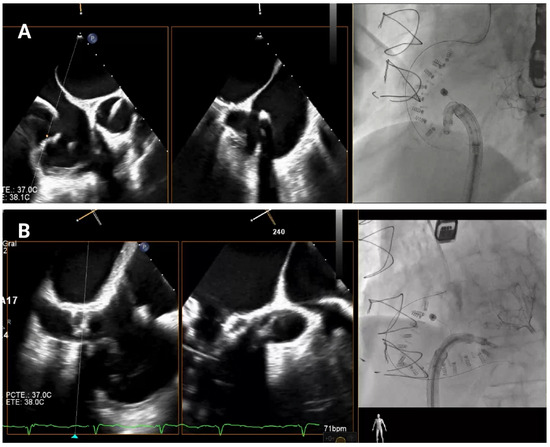

4.3.1. First Anchor Positioning (Anteroseptal Commissure)

The first anchor is positioned in the fibrous tissue anterior to the tricuspid annulus, close to the aorta, at least 25 mm from the center of aortic valve (

Figure 5A). The mid-esophageal right ventricular inflow-outflow view and transgastric right ventricular basal views are used to confirm the orientation of the IC [

4.3.2. Anterior Annulus Anchoring

Once the first anchor is released, the procedure progresses toward the anterior annulus (

Figure 5B). TEE views, such as the transgastric views at 40–60° and mid-esophageal views at 50–70°, provide crucial information for visualizing the IC’s position along the anterior segment of the annulus [

Figure 5.

Anterior tricuspid annulus anchoring. (A) First anchor placement in the fibrous tissue anterior to the tricuspid annulus, near the aorta. Orientation is confirmed using mid-esophageal right ventricular inflow-outflow and transgastric right ventricular basal views, along with fluoroscopy in an RAO projection. (B) Subsequent advancement of the implant catheter along the anterior annulus through transgastric and mid-esophageal views (40–70°) and multiplanar reconstruction.